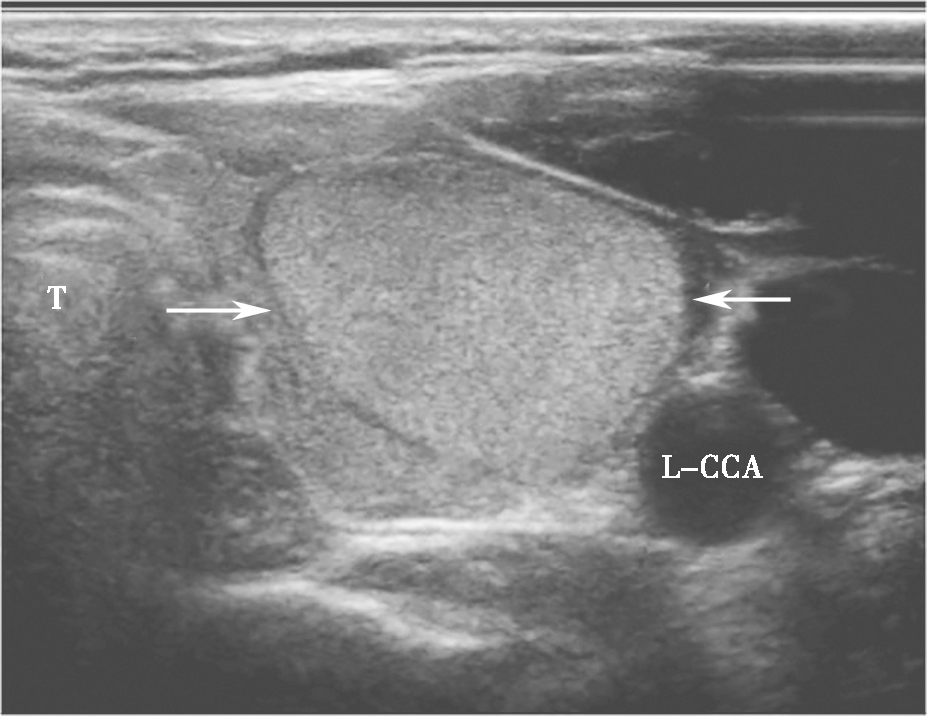

甲状腺腺瘤超声上表现为圆形或椭圆形中等回声或低回声,多伴薄声晕,肿物长轴常与腺体的长轴平行,较大者易合并囊性变、出血或坏死,内可有不规则无回声区、钙化灶或浓缩胶质,浓缩胶质表现为点状强回声后方伴“彗星尾”征,此为良性结节的特征性表现。多数腺瘤内部可见丰富规则的血流信号,周边常见较为完整的环绕血管(图7、图8)。

图7颈部正中偏左横切面:甲状腺左叶中等回声,形态规则、边界清晰,伴薄声晕(箭头所示)。T:气管;L-CCA:左侧颈总动脉

图8颈部正中偏左横切面(与图3-3-7同患者、同切面):中等回声可见丰富规则彩色多普勒血流信号(箭头所示)